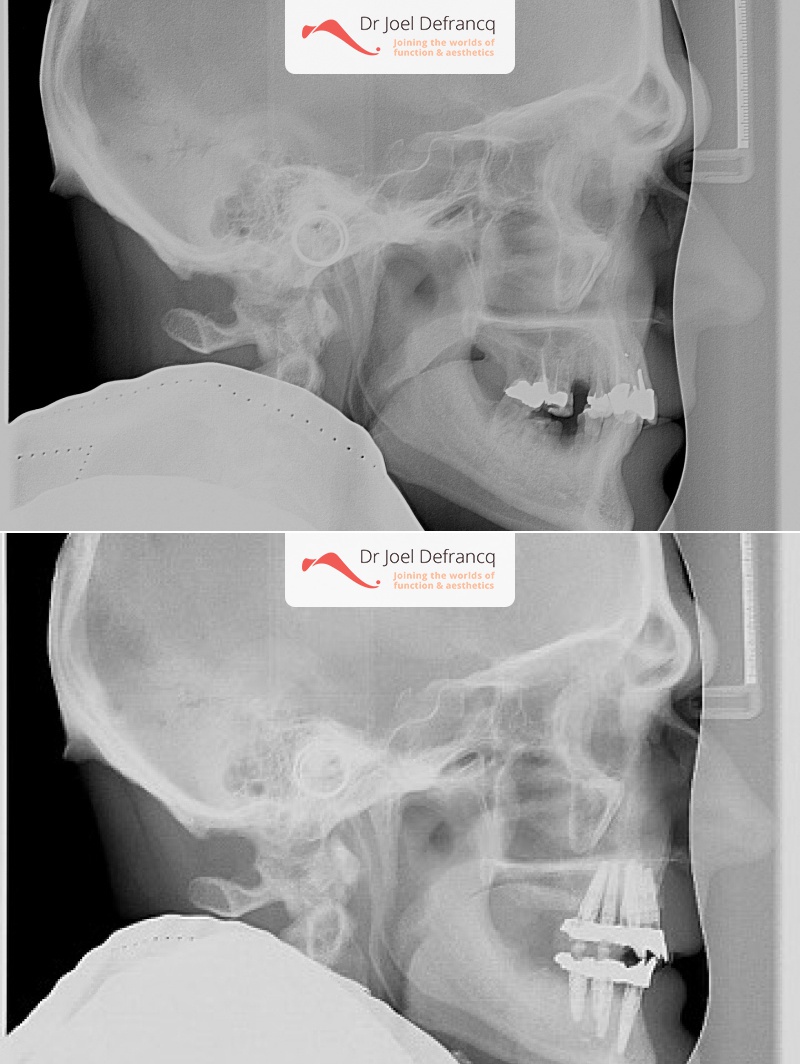

Veli: new teeth in a week - implants.

Behandeling tandheelkundige implantaten

- Vaste tanden op implantaten (bovenkaak)

- Vaste tanden op implantaten (onderkaak)